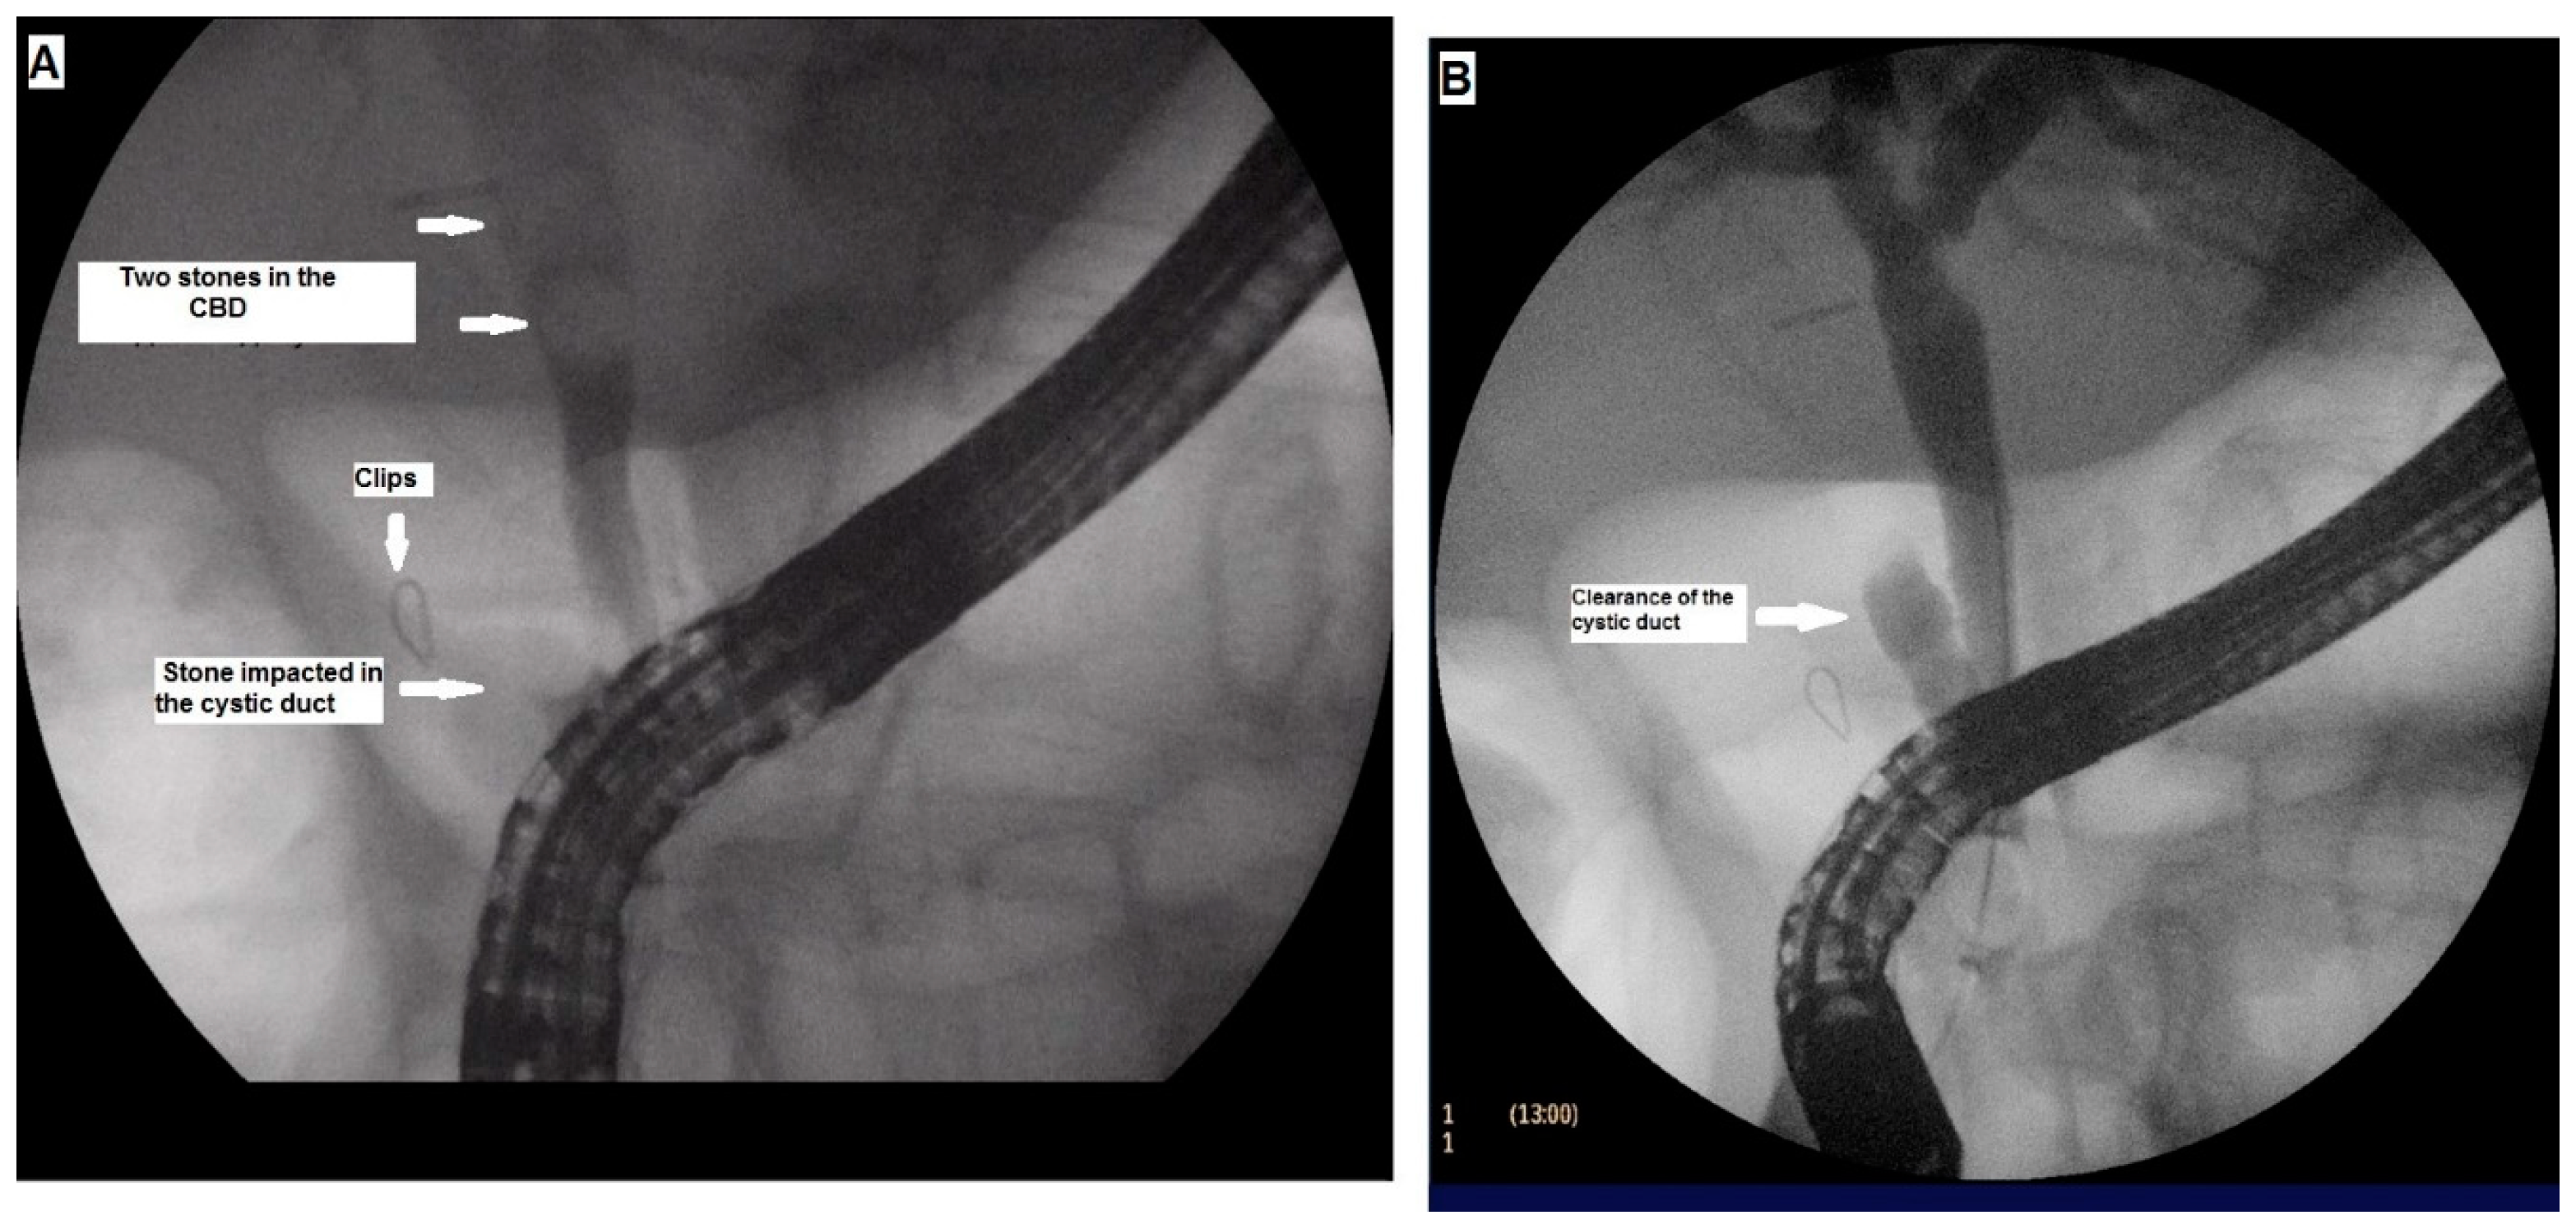

3.1. Case 1